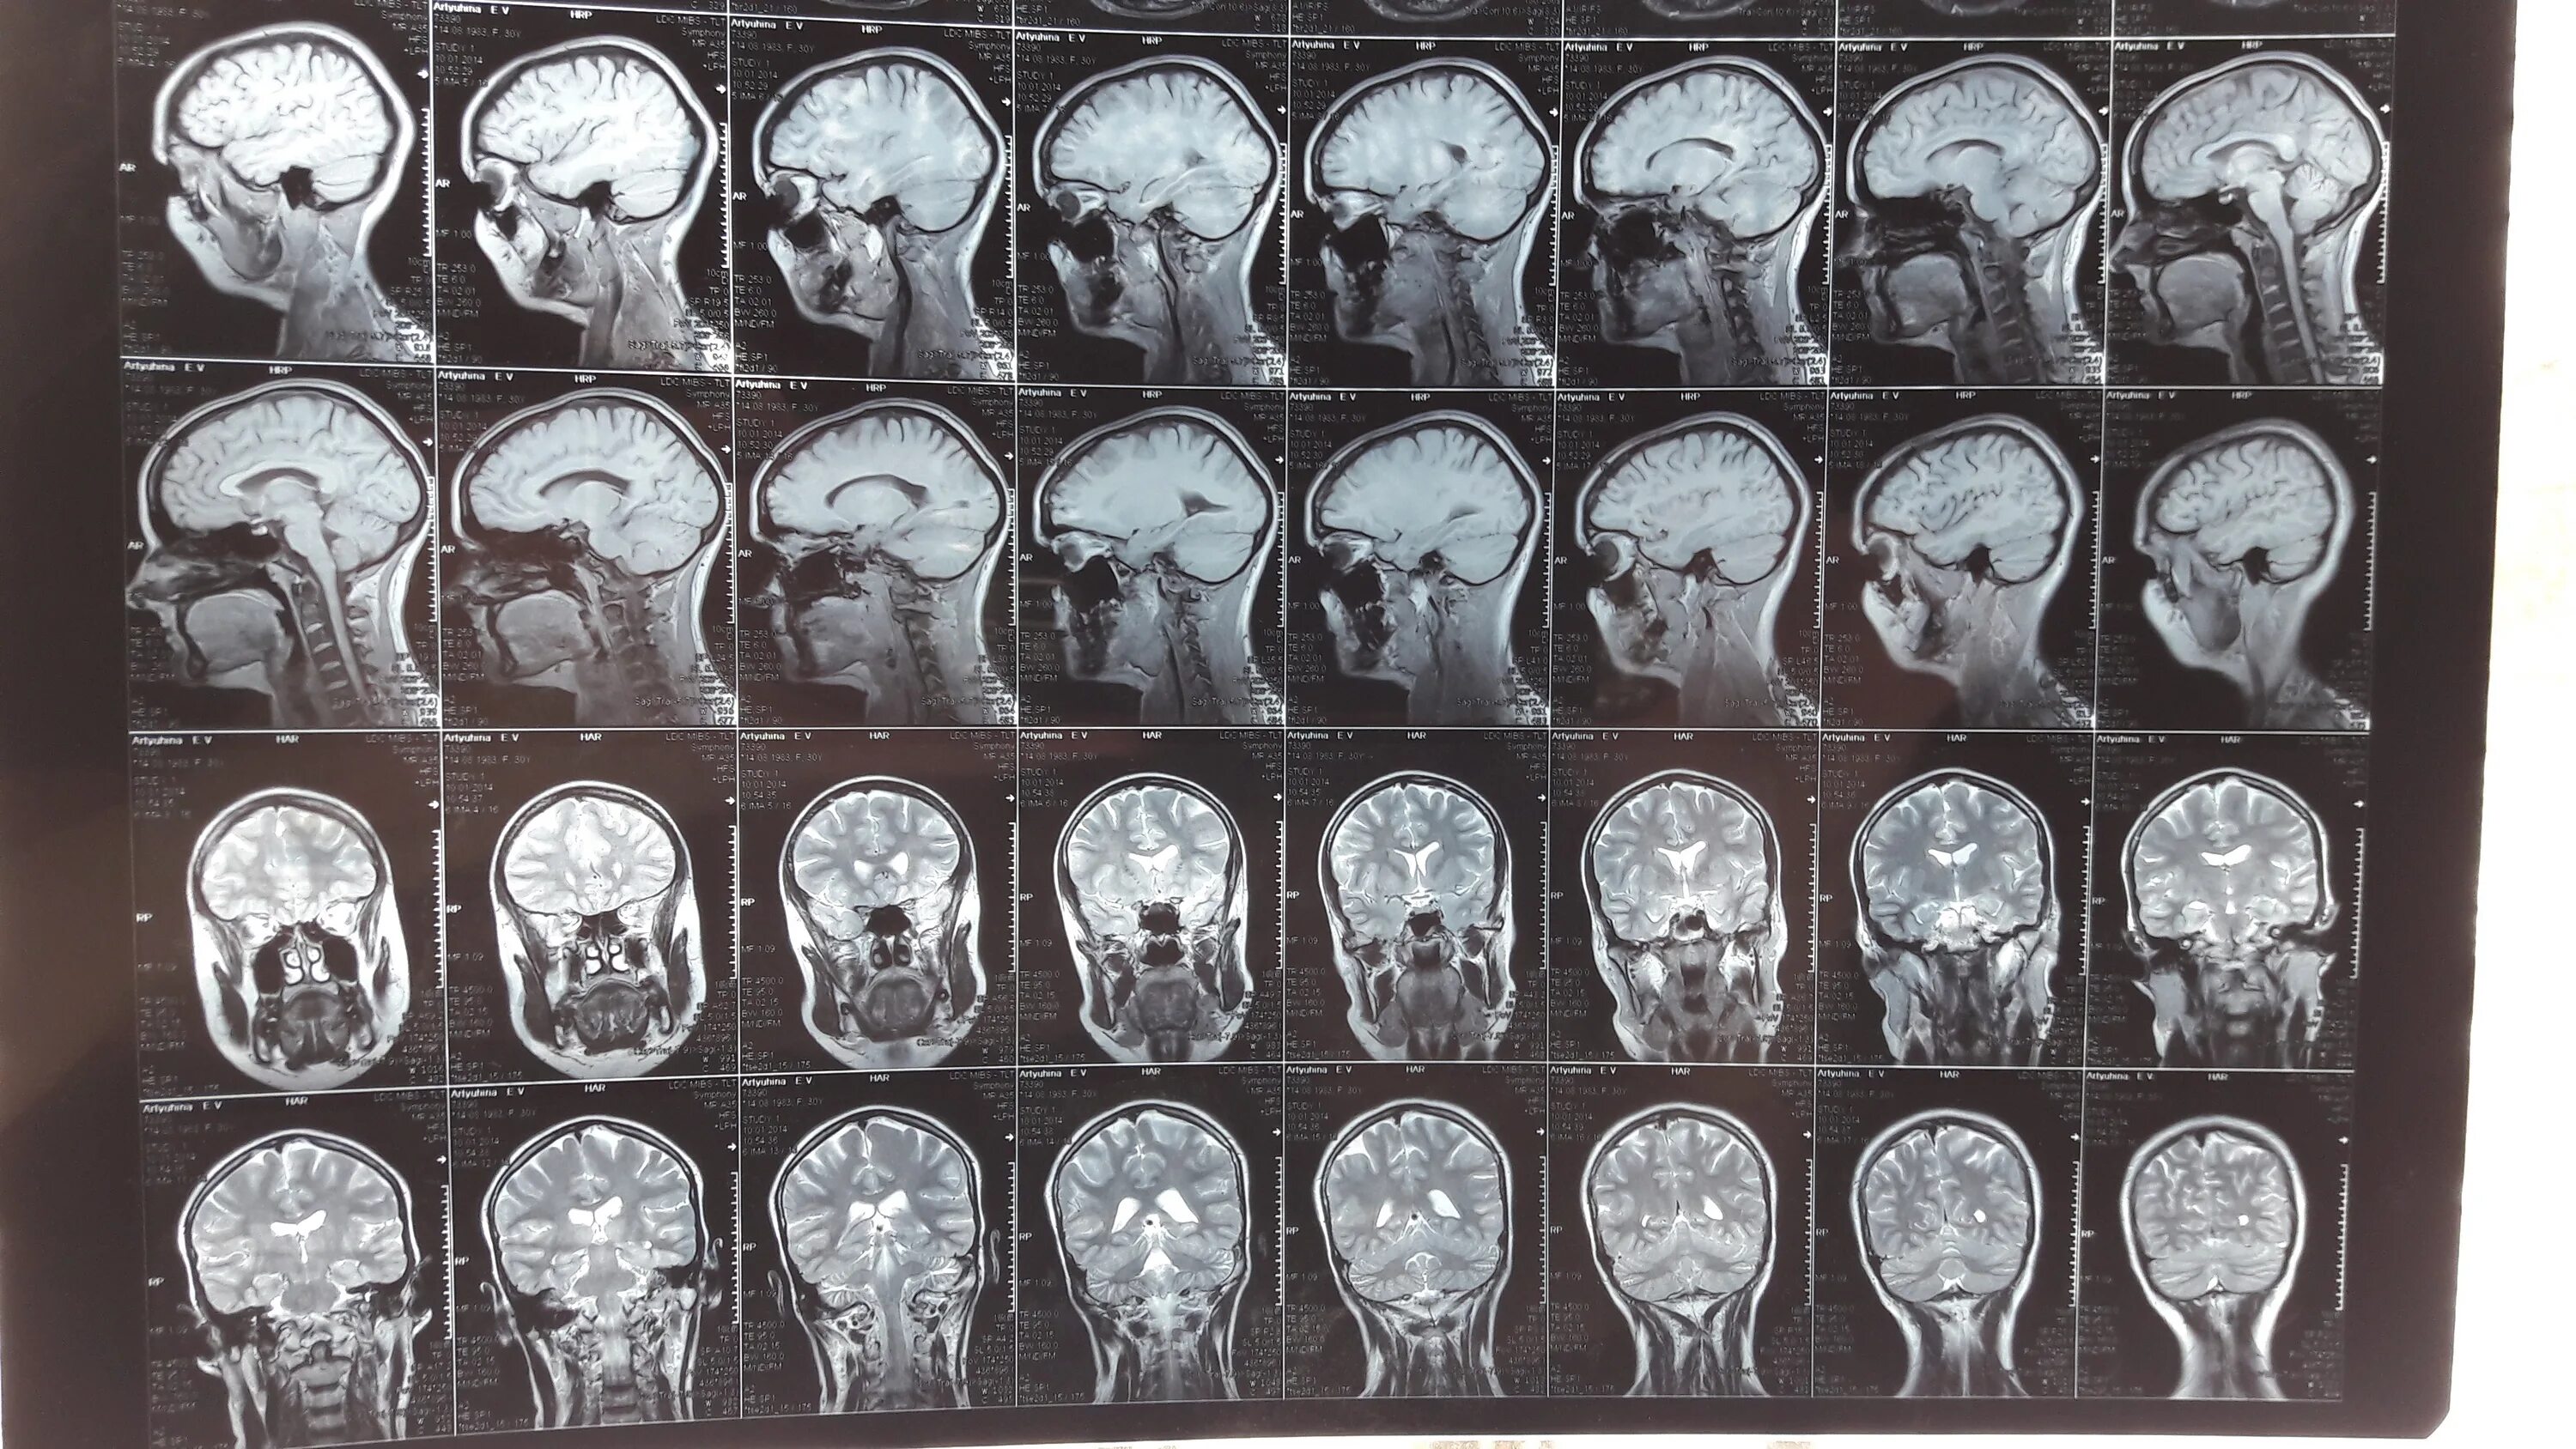

16 линия 81 мрт